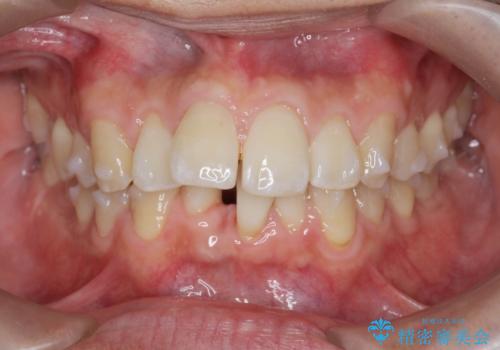

マウスピース矯正で前歯の角度、ガタガタをきれいに

- 突き出た前歯の角度、歯ブラシのしづらい前歯のがたつきの改善を希望され来院されました。

4本の小臼歯を抜きワイヤー矯正治療、下顎前歯を1本抜去しマウスピース治療のメリットデメリットを検討・相談し、より歯を抜く本数の少ないマウスピース矯正を行うこととなりました。

下顎の前歯は1本だけ抜去せざるをえませんでしたが、4本の小臼歯抜去とマルチブラケット矯正を回避することができ、治療結果・過程に満足いただくことができました。